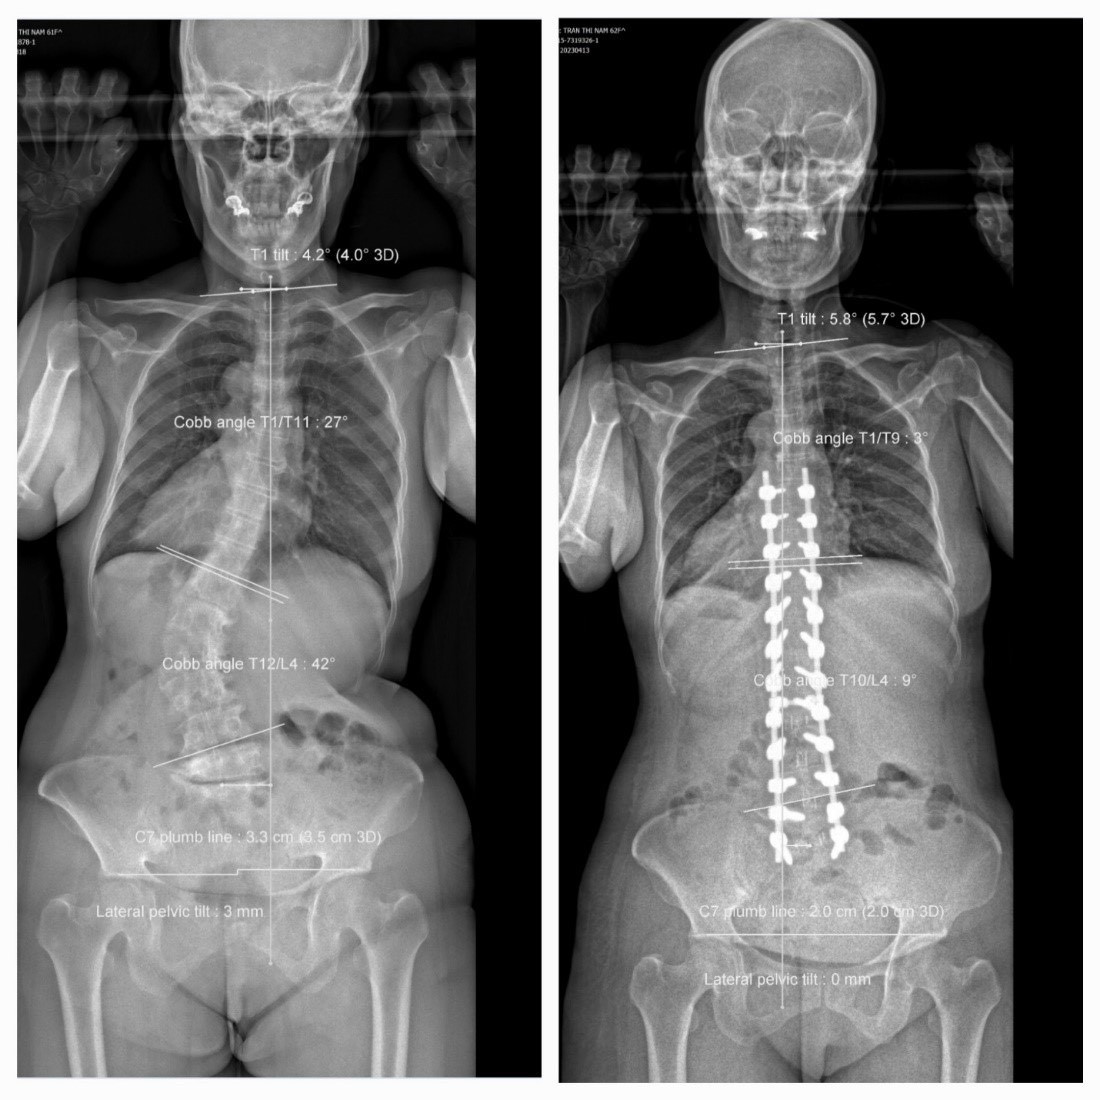

| Hình ảnh cột sống của bệnh nhân trước và sau phẫu thuật |

BS Nhựt Tâm cho biết, bệnh nhân đau nhiều vùng thắt lưng, lan xuống và tê bì hai chân, đi lại khó khăn, cúi ngửa đau tăng nhiều, chỉ đi bộ được vài mét. Kết quả chẩn đoán hình ảnh cho thấy bệnh nhân bị vẹo cột sống ngực - lưng – thắt lưng kèm theo còng cột sống, biến dạng khung chậu mức độ nặng khiến người bệnh mất thăng bằng toàn bộ cột sống. Bên cạnh đó, bệnh nhân còn bị chèn ép ống sống và rễ thần kinh.

Sau khi hội chẩn, các bác sĩ đã quyết định thực hiện phẫu thuật cho người bệnh. Ê kíp bác sĩ đã tiến hành phẫu thuật giải ép, ghép xương, cắt đĩa đệm hàn xương liên thân đốt cột sống thắt lưng, kết hợp nắn chỉnh đường cong trước sau cột sống thắt lưng bằng ốc chuyên dụng.

Sau ca phẫu thuật kéo dài hơn 7 giờ, bệnh nhân đã cao thêm được 8cm, dáng người đi thẳng. Bệnh nhân hết đau tê 2 chân, sức khỏe bình phục tốt.